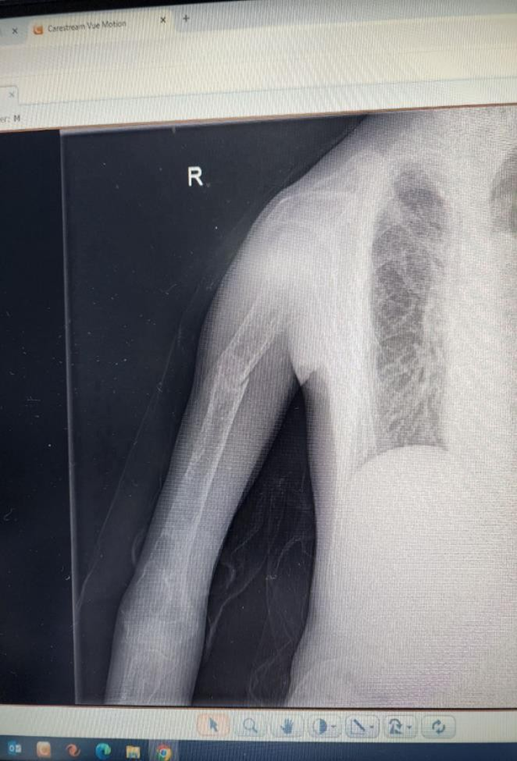

His recent condition started two months ago when he presented with a right humeral pathological fracture, which did not union after two months of management. Then, thorough investigations were done to determine the cause of his pathological fractures. His laboratory test is shown in Table 1. His chest x-ray showed osteoporotic features. His extremities and vertebrae showed osteoporotic features. At the T99m MIBI nuclear scan, a focal and persistent active spot at the lower pole of the right thyroid gland, consistent with parathyroid adenoma, was detected (Figure 2).

Figure 3